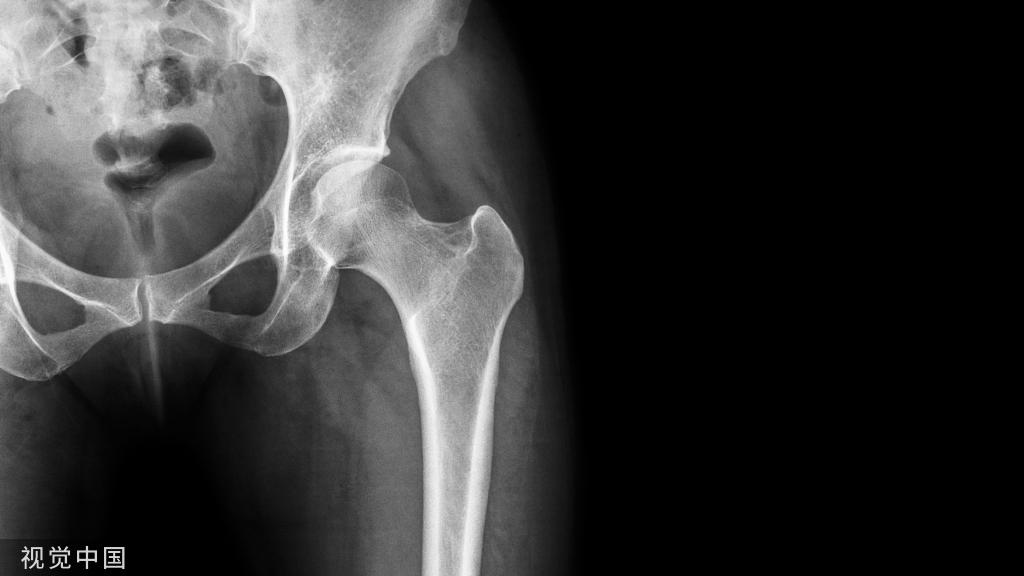

X线:骨盆正位片为常规检査。在患侧坐骨耻骨结合处可见到骨皮质膨隆,有时出现层状改变,膨隆部位密度浓淡不均,中央可见类圆形透光区,偶有骨皮质破裂影像,膨隆周围可见硬化改变。